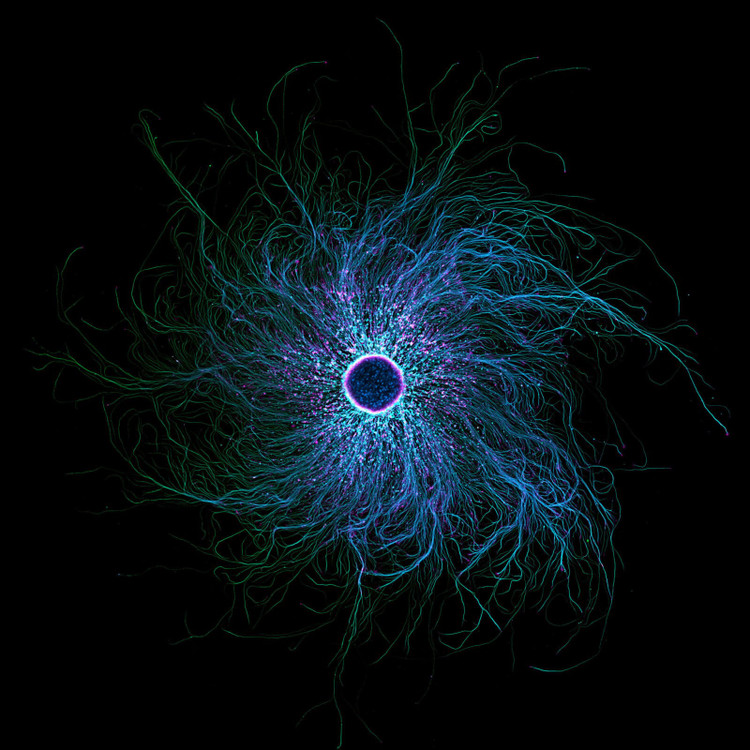

Kadangkala, imej dunia mikroskopik mengkhianati kesan awal. Walaupun imej ini kelihatan seperti lubang hitam yang mengamuk, subjek foto, yang diambil oleh Stella Whittaker dari Institut Kesihatan Nasional (NIH), sebenarnya adalah neuron deria yang diperoleh daripada iPSC, yang dilabelkan untuk menunjukkan dua protein, tubulin dan aktin. Whittaker menggunakan gabungan teknik mikroskop untuk mencipta imej yang mengejutkan ini.